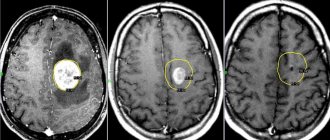

Контрольное МРТ предпочтительно выполнять не ранее, чем через 3 месяца после операции, чтобы исключить ошибочную трактовку данных в связи с присутствием свежих послеоперационных изменений. При оценке послеоперационных МРТ необходимо также учитывать использование в ходе операции гемостатических материалов.

Удаление каверномы островка с хорошим исходом